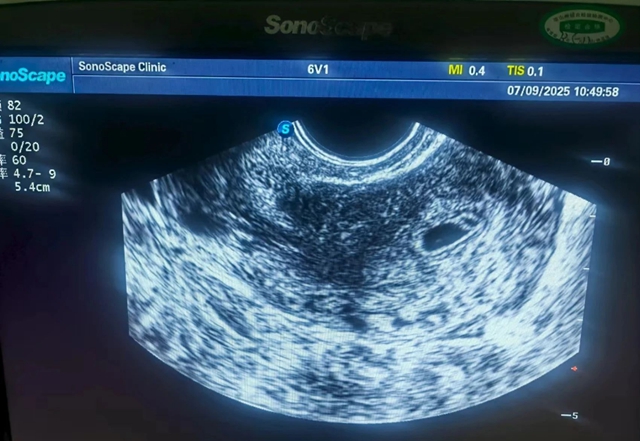

经过3个月的综合治疗后,马海女士第一次促排卵就成功了,顺利怀孕,停经40天时,彩超提示:宫内妊娠。李娟医生继续为其通过中药补肾安胎,并配合黄体酮进行保胎治疗。